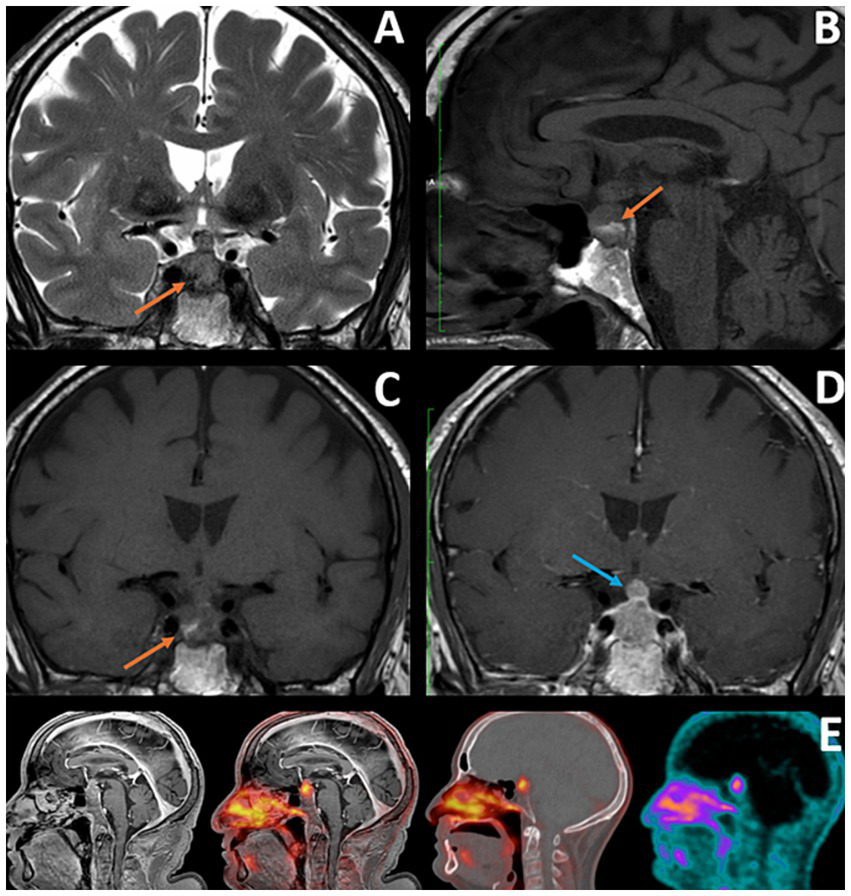

Following these findings, the patient underwent pituitary MRI (Figure 2), which showed an intra-sellar tissue lesion extending to the supra-sellar region, with a mass effect to the optic chiasma and in close proximity to internal carotid arteries, displaying heterogeneous signal intensity on T1- and T2-weighted MRI, with hemorrhagic components and mildly heterogeneous contrast enhancement. These imaging findings were compatible with a pituitary macroadenoma.

Figure 2

(A–C) Coronal T2, Sagittal, and Coronal T1: Orange arrows showing hemorrhagic component within the lesion, with hypointense signal in T2 WI and hyperintense signal in T1 WI (consistent with subacute character), which could be consistent with recent apoplexy of pre-existing pituitary adenoma (factor contributing to the initial misdiagnosis). (D) Coronal T1 with Gd: Blue arrow showing a nodular component of the lesion at the level of the pituitary stalk, a feature that, according to some researchers, may facilitate correct diagnosis of pituitary metastases. (E) IRM T1 TFE Gd; Fusion image PET/MRI; fusion image PET/CT; PET.